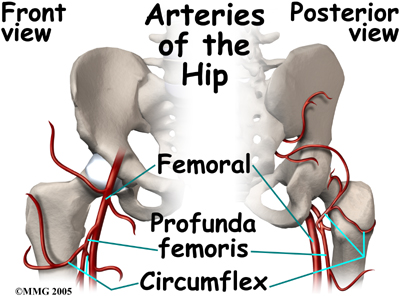

The capital femoral epiphysis is somewhat unique. It is one of the few epiphyses in the body that is inside the joint capsule. (The joint capsule is the tissue that surrounds the joint.) The blood vessels that go to the epiphysis run along the side of the femoral neck and are in danger of being torn or pinched off if something happens to the growth plate. This can result in a loss of the blood supply to the epiphysis.

Perthes disease results when the blood supply to the capital femoral epiphysis is blocked. There are many theories about what causes this problem with the blood supply, yet none have been proven. There appears to be some relationship to nutrition as children who are malnourished are more likely to develop this condition.

Children who have abnormal blood clotting (a condition called thrombophilia) may also have a higher risk of developing Perthes disease. These children have blood that clots easier and quicker than normal. This may lead to blood clotting that blocks the small arteries going to the femoral head. As a result of new evidence, the certainty of thrombophilia as a cause of Perthes is now under debate. This will remain an area of study until scientists clear up the significance of thrombophilia as a possible cause of Perthes.

Children who have abnormal blood clotting (a condition called thrombophilia) may also have a higher risk of developing Perthes disease. These children have blood that clots easier and quicker than normal. This may lead to blood clotting that blocks the small arteries going to the femoral head. As a result of new evidence, the certainty of thrombophilia as a cause of Perthes is now under debate. This will remain an area of study until scientists clear up the significance of thrombophilia as a possible cause of Perthes.